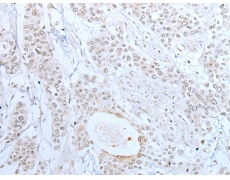

IHC positive control: |

Human prostate cancer and human tonsil |